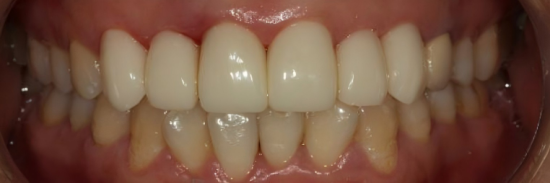

VSです。

暫定復元形態、日陰、歯肉の調和が改善されています。